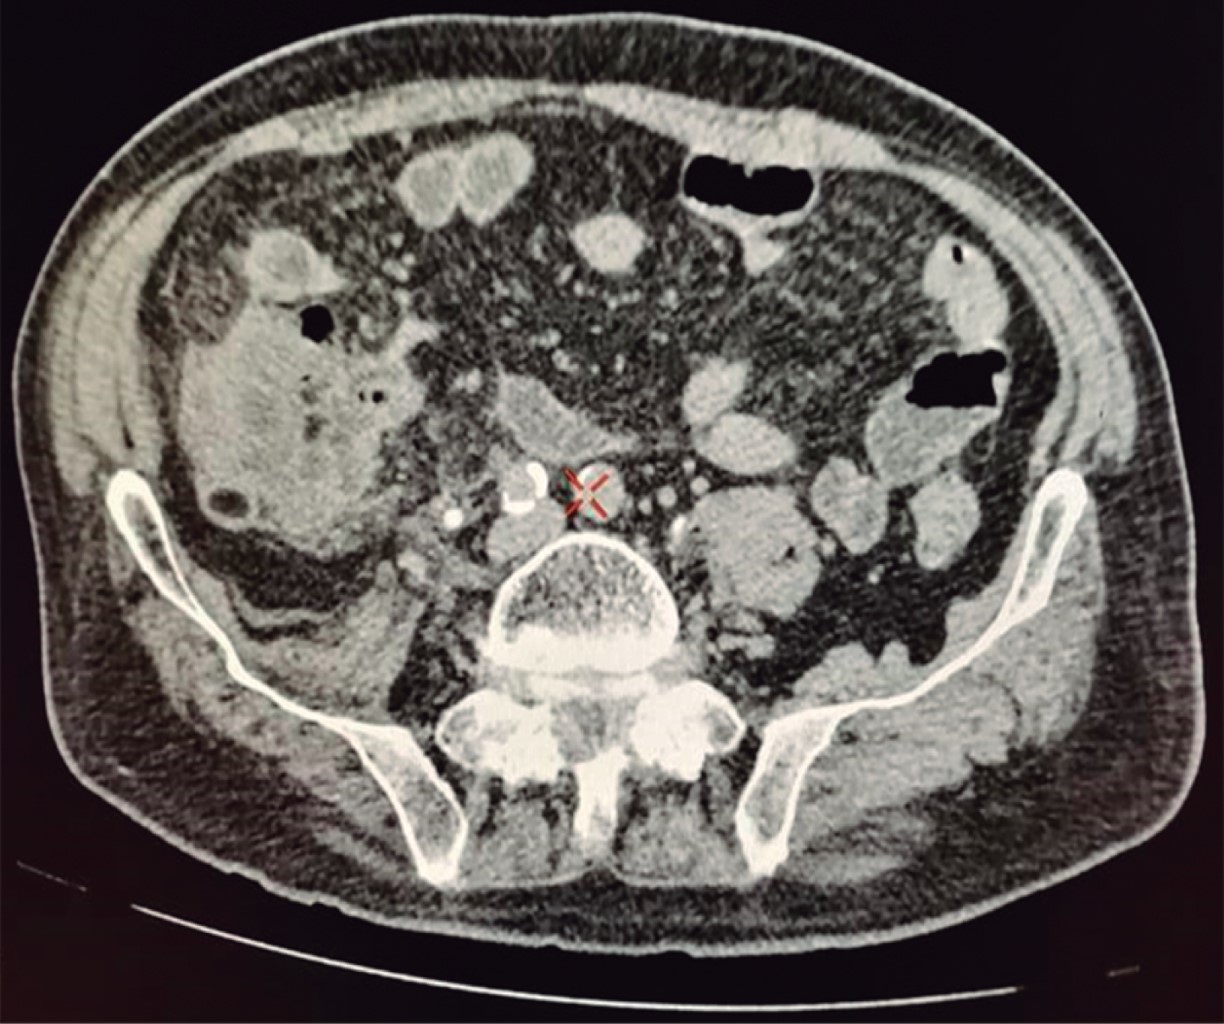

Hombre en la novena década de la vida, con dolor abdominal de 72 horas de evolución, con predominio a nivel de la fosa iliaca derecha (FID), asociado a episodio de bacteriemia, hiporexia, náusea, vómito y evacuaciones líquidas. Abdomen con dolor a la palpación en la FID, apendiculares positivos, peristalsis presente e hiperactiva, con datos de irritación peritoneal. Leucocitosis de 11.2 × 103 ul, con desviación a la izquierda: neutrofilia de 86.9%. La tomografía abdomino-pélvica con medio de contraste intravenoso (Figura 1) mostró el apéndice cecal con datos de proceso inflamatorio agudo. Se realizó apendicectomía abierta por incisión tipo McBurney. Al ingresar a la cavidad abdominal se encontraron de manera incidental tres cuerpos peritoneales libres, los cuales se enviaron a estudio histopatológico, junto con el apéndice cecal resecado (Figura 2).

Se han propuesto diferentes teorías sobre el origen de estos cuerpos peritoneales libres, pero su etiología exacta es aún desconocida. Dentro de los posibles orígenes se incluyen apéndices epiplóicos, epiplón, anexos autoamputados o tejido adiposo pancreático; la teoría más aceptada es la que menciona que se originan de apéndices epiplóicos.3 El primero en describir los apéndices epiploicos fue Andre Vesalius, posteriormente diversos estudios anatómicos fueron realizados para describir otros aspectos anatómicos de los mismos. El primero en reportar una serie de casos de apéndices epiploicos libres fue Harrigan en el año de 1917.5 La teoría sobre los cambios secuenciales que llevan a su formación fue presentada por Virchow en 1863, donde fue propuesto un aumento gradual y progresivo de tejido graso dentro de un apéndice epiplóico (por lo general en el contexto de obesidad) lleva a la obliteración y obstrucción de los vasos sanguíneos del pedículo; después se presenta un proceso de torsión, estrangulamiento y necrosis del apéndice epiplóico, hasta su amputación.2 Posteriormente, en 1933, Patterson propuso que la isquemia es el factor etiológico predominante en su fisiopatología y que es la causa que conlleva a infarto del apéndice epiploico. Es el factor etiológico dominante en la fisiopatología, y que es dicha isquemia la que lleva al infarto y la amputación.4 Una vez que el apéndice epiplóico queda flotando libre en la cavidad abdominal, sufre un proceso de saponificación y calcificación.6 Con el paso de los años, la reacción peritoneal sobre este cuerpo libre y la deposición a su alrededor de líquido peritoneal (fluido sérico exudativo rico en proteínas, principalmente albúmina) produce el progresivo incremento en su tamaño mediante adición de capas fibrosas periféricas.2,4 Esta teoría fue comprobada en 1968 por Donado y Kerr quienes tomaron grasa peri-uterina de cuyos y la colocaron en la cavidad peritoneal de dichos animales, generando típicos cuerpos peritoneales libres cada vez más grandes con el paso del tiempo.7 Una vez formados, establecer un diagnóstico preoperatorio correcto resulta difícil, y en muchas ocasiones se confunden con neoplasias y se resecan innecesariamente. Son lesiones raras y asintomáticas, pero en ocasiones pueden ser detectadas por estudios de imagen. En tomografía computarizada se observan como masas, usualmente únicas, de forma redonda u ovalada, bien definidas, con calcificación central, rodeadas por un tejido blando periférico. En resonancia magnética se observan como masas bien circunscritas, hipointensas en T1 y T2, pero con un área de hiperintensidad central en T1. Por ninguna modalidad de imagen la masa presenta reforzamiento a la administración de medios de contraste, dado que carecen de aporte vascular.1 Si se realizan estudios de imagen seriados o en diferentes posiciones (supina o prona), al compararlos se puede apreciar la movilidad de la masa, evidenciando ubicaciones variables dentro de la cavidad.1,7 Se debe realizar un adecuado diagnóstico diferencial con enfermedades benignas (leiomiomas, rabdomiomas, teratomas, fibromas), enfermedades malignas (cáncer colorrectal, cáncer de ovario, linfomas, metástasis), cálculos urinarios, biliares o apendiculares, quistes dermoides, granulomas tuberculosos, calcificación de ganglios linfáticos, cuerpos extraños, quistes hidatídicos, entre otros.3,7 Si se detectan de forma incidental en cirugía, situación que ocurrió en nuestro caso, los cuerpos peritoneales libres flotan dentro de la cavidad peritoneal y tienen aspecto de una concreción blanca, dura y brillante que da la apariencia de un huevo cocido.1,8 La extirpación quirúrgica con subsecuente examen histológico puede confirmar definitivamente el diagnóstico en función de las características morfológicas. Dichos hallazgos patológicos consisten en un núcleo central de grasa necrótica calcificada, laminada por capas de tejido fibroso acelular hialinizado en la periferia,1,2 como lo evidenciamos en los cuerpos encontrados en nuestro paciente. De lograrse un adecuado diagnóstico preoperatorio, por lo general los cuerpos peritoneales libres no requieren tratamiento y se manejan sólo con vigilancia.2 Es esencial que los médicos conozcan esta entidad y sus características en estudios de imagen, así como su posibles diagnósticos diferenciales, para con un alto índice de sospecha poder establecer el diagnóstico correcto y evitar intervenciones innecesarias, dado que se trata de neoformaciones benignas que pueden ser manejadas mediante vigilancia.